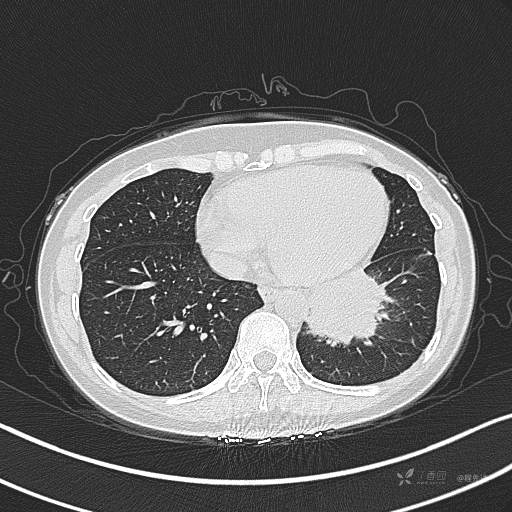

CT平扫

肺窗